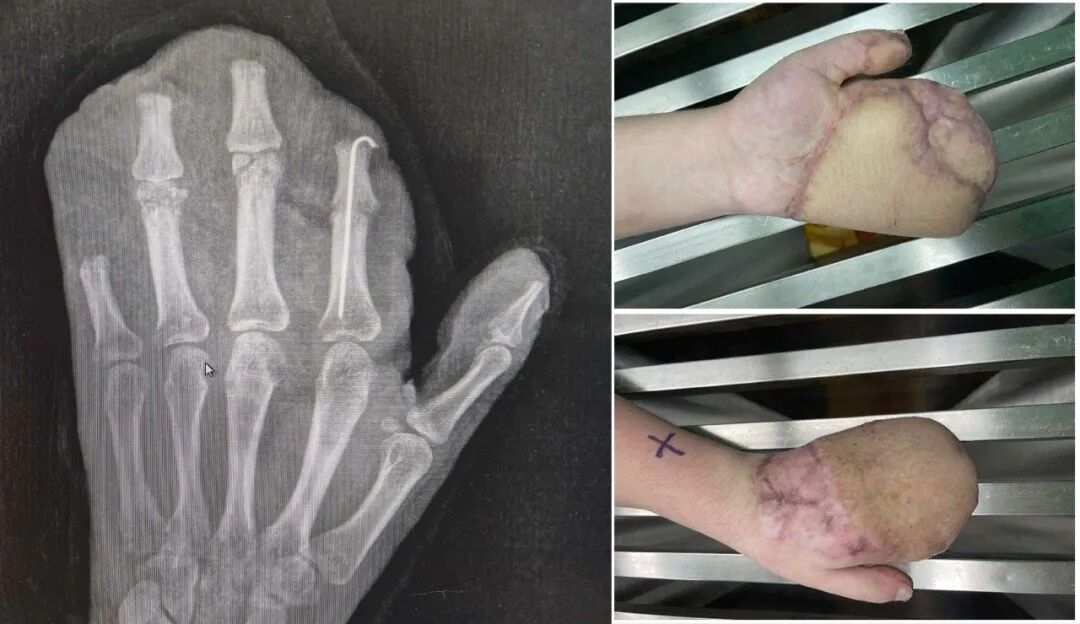

为覆盖巨大创面,医生启用了经典的“腹部带蒂皮瓣”,将断手“寄养”在了带有自身血供的腹部皮肤上,为后续所有修复提供了生存的土壤。

经过近一个月的“腹手相连”,皮瓣在手部建立了新的血运。医生们进行了“断蒂”手术,让手从腹部独立,患者也获得了活动自由,为功能锻炼打下基础。

等待皮瓣完全稳定后,医生们开始了功能重塑。手术将臃肿的皮瓣进行修薄塑形,并进行了首次分指术,把粘连在一起的手指分开,同时取出了已愈合的骨折内固定物。

完美的指蹼(手指间的缝隙)是手指灵活张开与并拢的关键。为进一步改善外观与功能,今年1月11日,医院为他实施了二次分指与指蹼重建术,使用更精密的局部皮瓣,重建出更自然、更深的指蹼,让每根手指都能更独立。